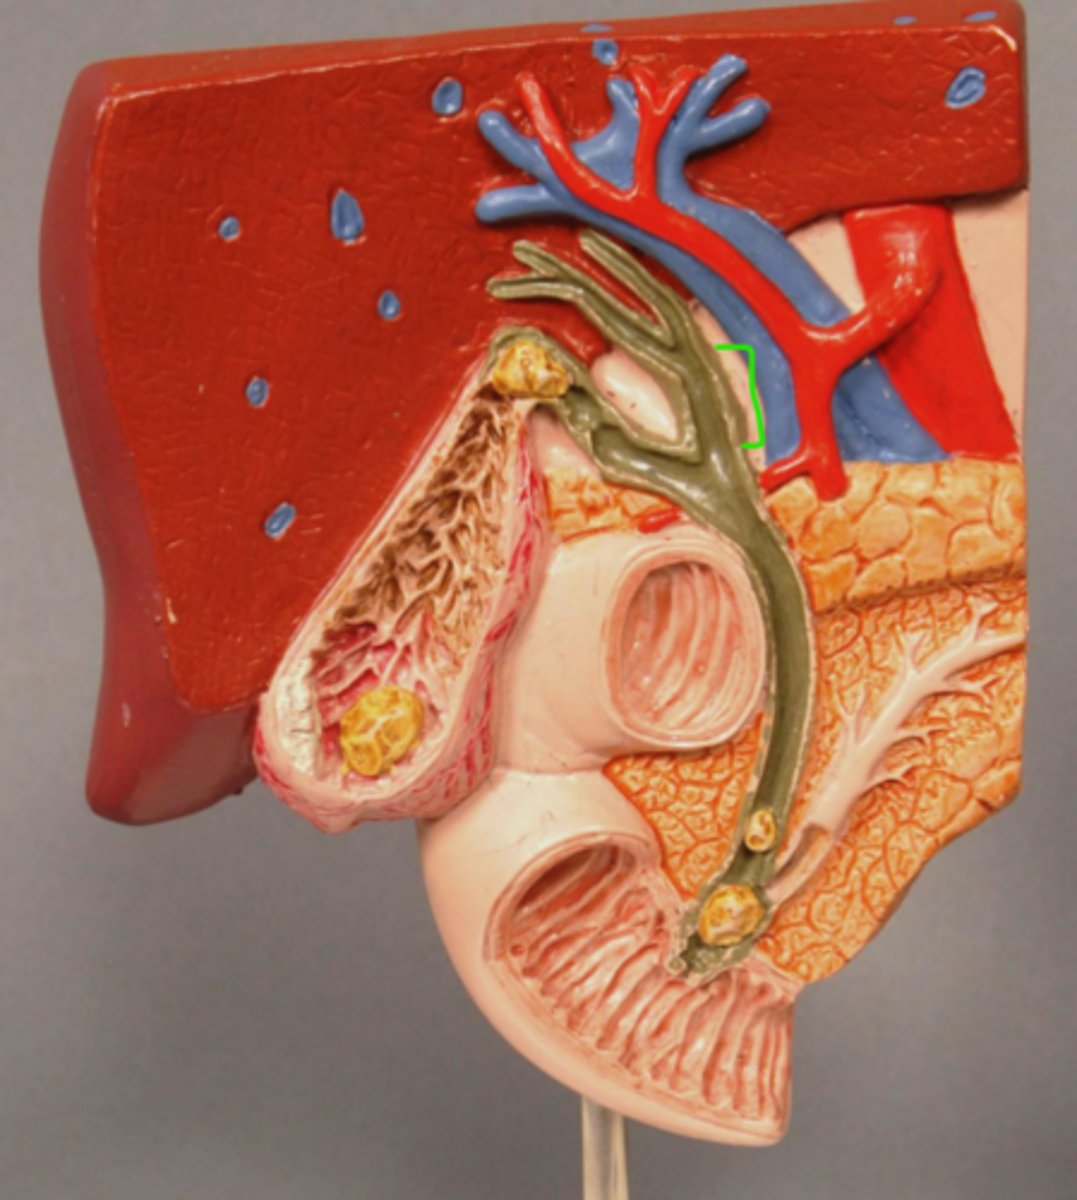

Gallstone Model

Common Bile Duct

Sphincter of Oddi

Pancreatic Duct

Gallstone in Bile Duct

Gallstone in Ampulla of Vater